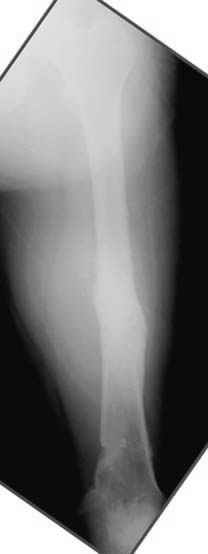

Несколько снимков из моей коллекции, чтобы разьяснить, почему мы до сих пор делаем различные варианты остеотомии.

На рисунке N1 предоперационный план лечения ложного сустава шейки бедра- линия ложного сустава, угол и направление введения импланта, клиновидная остеотомия в градусах и миллиметрах, второй снимок после коррекции, расчет, на сколько удлиняется конечность и размеры импланта;

N3 рисунок окончательный снимок, после операции моя рентгенограмма должен выглядеть примерно как эта картина. На N4 снимке клин перед удалением; N5 послеоперации 3 нед.; N6 окончательная рентгенограмма.

Djoldas Kuldjanov 23 Ноябрь 2004, 18:21

пластическая модель; и коррекция бедра аппаратом Илизарова.